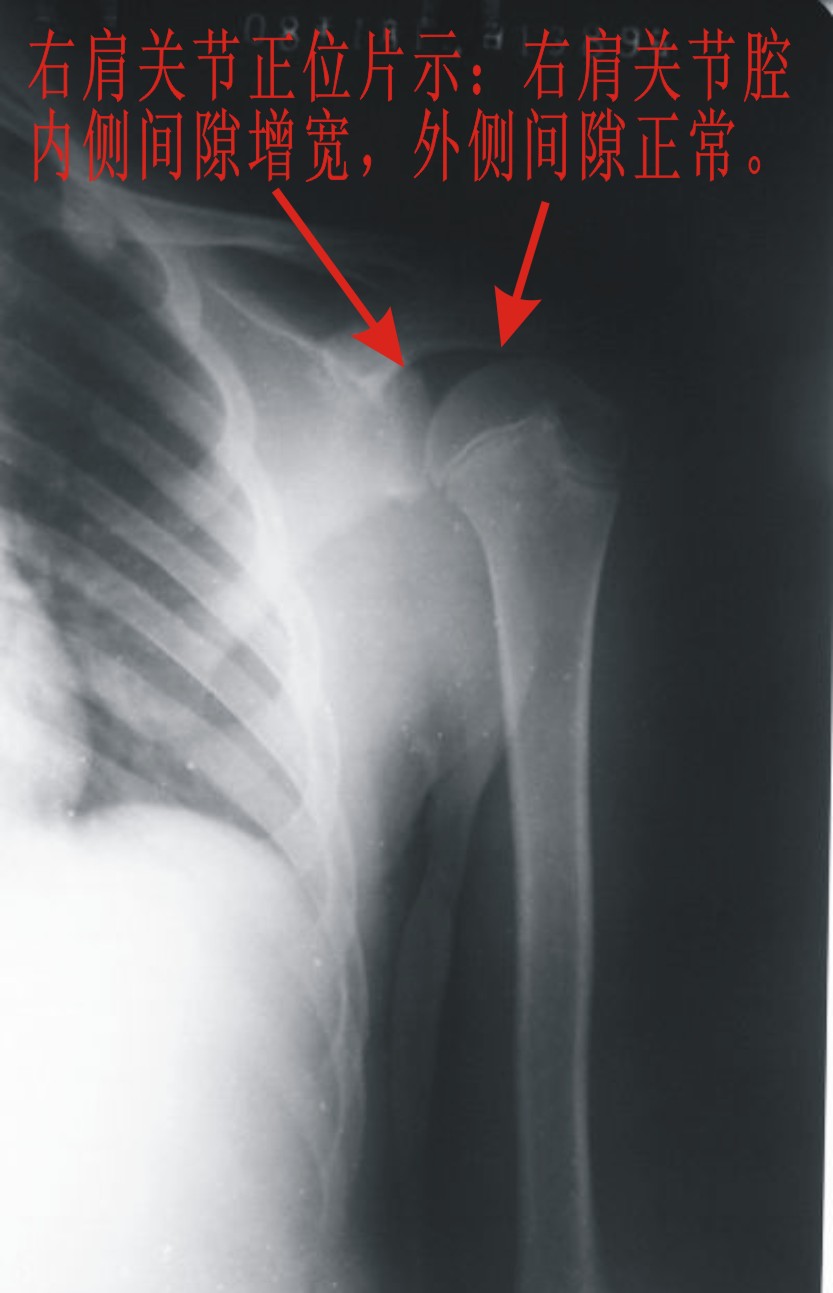

患者,男,13岁。自诉两月前双肩关节时有弹响,有时左、右肩关节轮换隐痛。但双上肢能抬举、左右旋转、屈伸自如。pe:双肩及双上肢皮肤无红、肿。触诊:双肩关节区域有抖动,似触心脏的搏动感,但抖动、搏动感能自控。双肩区域皮肤无发热。听诊:用耳贴近患者双肩区能听到弹响声。x线胸部后前位示:双肩关节间隙增宽,考虑双肩关节半脱位。双肩关节正侧位片示:双肩关节无明显脱位征象。双肩关节区域透视示:双肩关节解剖位时,双肩关节间隙增宽(与胸部后前位的双肩关节间隙相等),也能见双肱骨头在双肩关节腔内上、下移动约1cm左、右。但患者能自控(双肱骨头在双肩关节腔内不上、下移动)。请战友们详见患者相片、胸部后前位片、双肩关节正侧位片。我第一次碰到这样的病例(是否是神经性关节病“夏科氏关节”?),经验不足,希望能帮助诊断。亦请分析病因、病理机制,是什么原造成的?最好能提供治疗方法,谢谢!

双侧肩关节解剖位时,双肩关节间隙增宽,但肱骨头及周边骨质 关节腔均未见异常。与骨科专家会诊结果,目前只能诊断:肩关节松弛症!

双肩关节间隙增宽,但肱骨头及周边骨质 关节腔均未见异常。